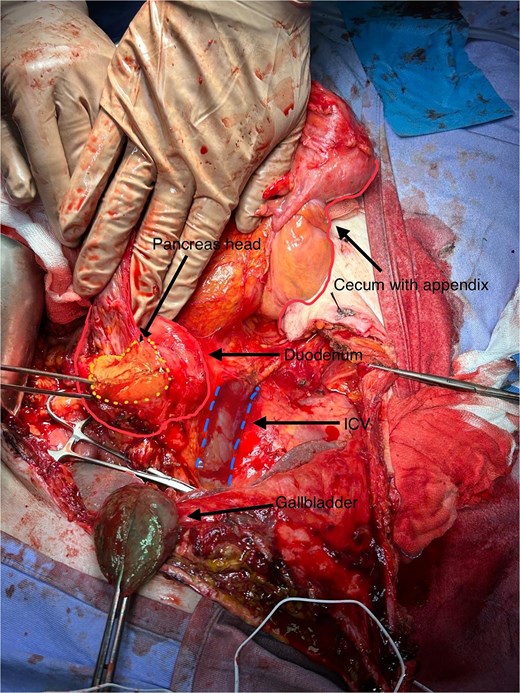

In this patient, median laparotomy was enabled by inverted-L incision, exposing a kissing ulcer during abdominal exploration (Fig. 1). Total mobilisation of ascending colon and caecum (Cattel-Braasch manoeuvre) and a complete Kocher manoeuvre were performed (Fig. 2). Cholecystectomy was also done with retention, thus serving for upper liver traction (Fig. 2). Once an enterostat was positioned just distal to the posterior peptic ulcer (Fig. 3a), a catheter was inserted through cystic duct to radiographically localise papilla of Vater during surgery. We injected contrast medium through the biliary catheter (with enterostat closed) to visualise the second and third parts of duodenum and confirm integrity of the papilla (Fig. 3b).

Total mobilisation of ascending colon and caecum (Cattel-Braasch manoeuvre) and complete Kocher manoeuvre, with inferior vena cava (IVC) and aorta exposed, leaving gallbladder in place for liver traction.